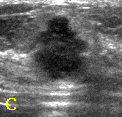

- 여자 40세, 정기 검진을 위하여 내원

유방촬영술(좌측)에서 양측유방은 치밀유방이었으며 유방암의 소견은 없었다. 그러나 동시에 시행한 초음파검사(우측)에서 5mm크기의 유방암(화살표)을 발견하였다. 이와 같이 치밀유방에서는 유방촬영술의 예민도가 감소한다. 이러한 경우 유방촬영술의 보조적인 검사로 유방초음파를 병행하면 유방암의 발견율을 높일 수 있다.